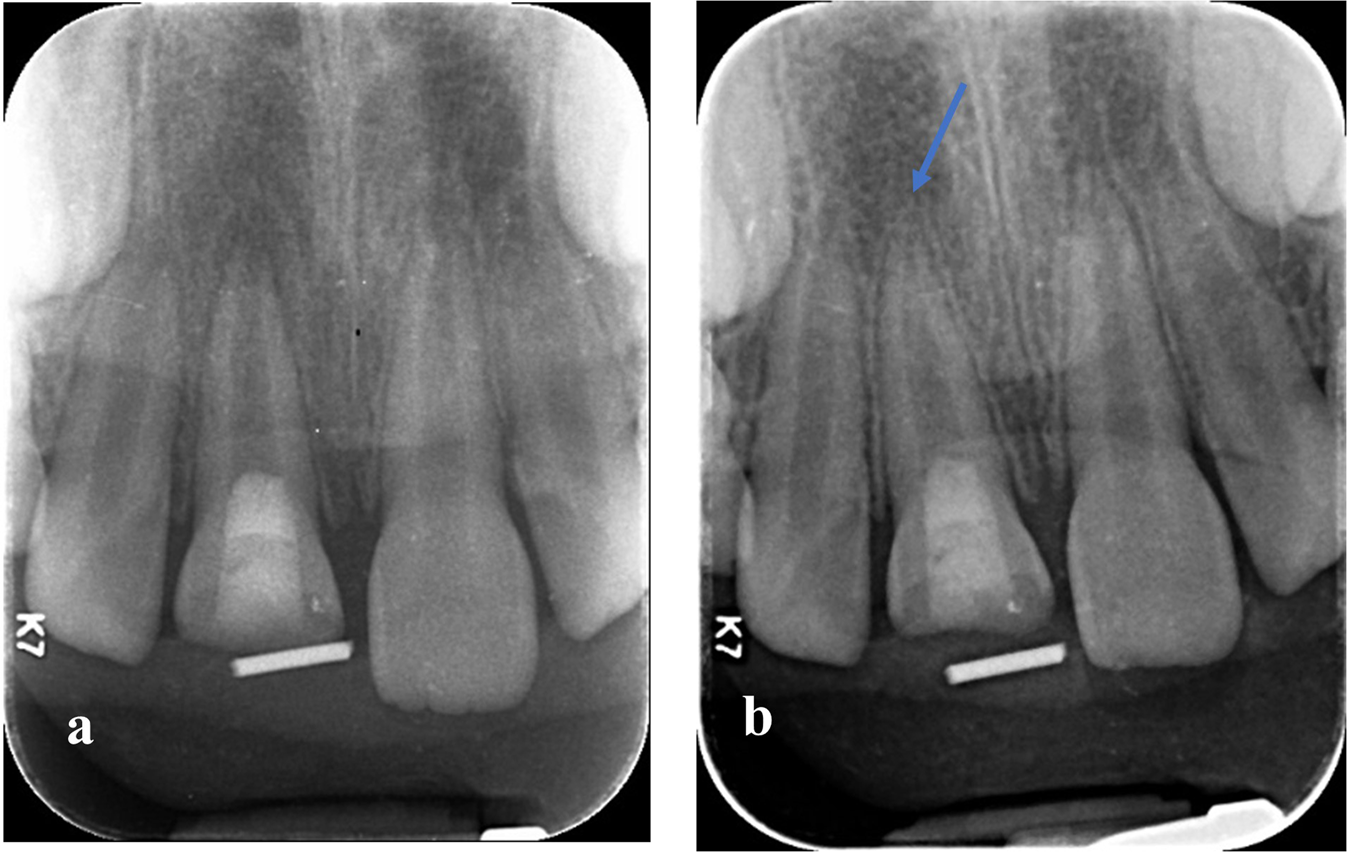

Fig. 8: Digital periapical radiographic images of immature upper right central incisor representative for Group (W) showing continuing root lengthening.

a Baseline immediate post-operative radiograph showing the immature root of upper right central incisor. b 12 months follow-up radiograph showing the increase in root length in upper right central incisor.